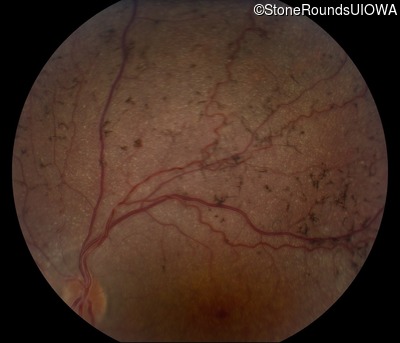

Fundus Photography - Right - 20/200 +1

Exemplar